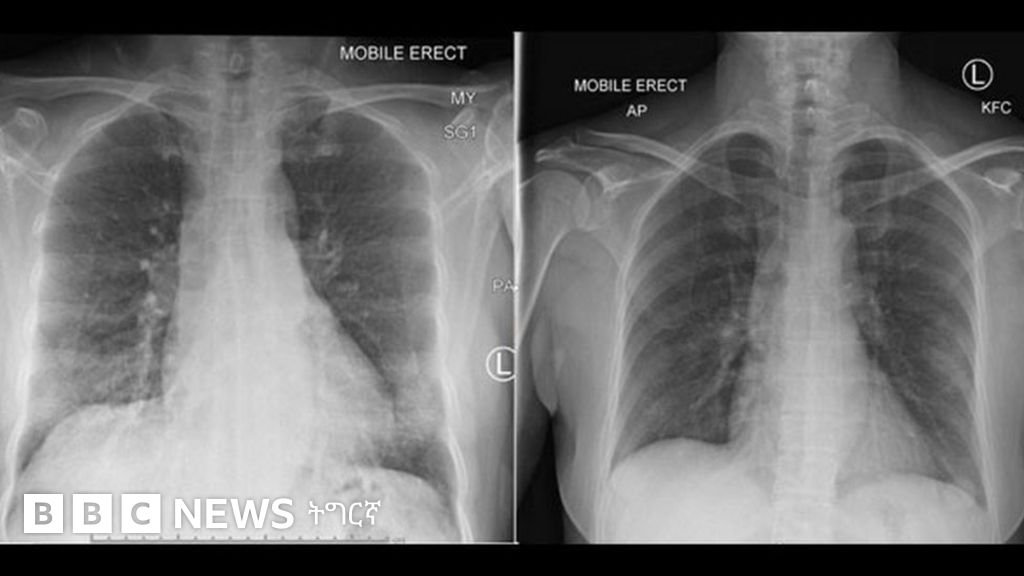

ካብ ቻይና ውሃን ዝመጽአት ጓል 47 ዓመት ጓል ኣንስተይቲ፡ ኣብ ሆስፒታል ኣውስትራሊያ ሕክምና ክትረክብ ድሕሪ ምጽናሕ፡ ኣብ ውሽጢ 14 መዓልታት ድሒና።

ፕሮፌሰር ካትሪን፡ ኣብዛ ውልቀሰብ ድማ፡ እቲ ሕማማት ዝከላከል ክፍሊ ሰብነታ ምምሕያሽ ከም ዘርኣየ ክንዕዘብ ክኢልና ኢና ኢላ።